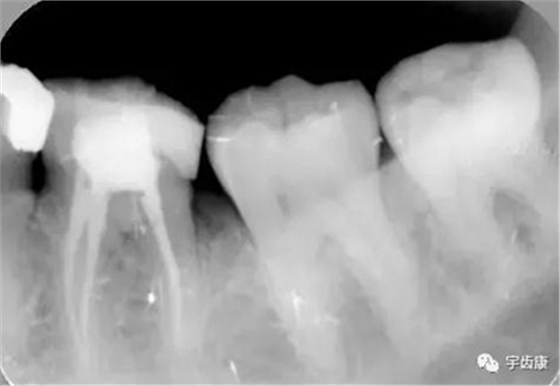

樁固位形(增加固位形和抗力形)

X線閱片知識

烤瓷牙結(jié)構(gòu)知識

烤瓷牙的設(shè)計方式